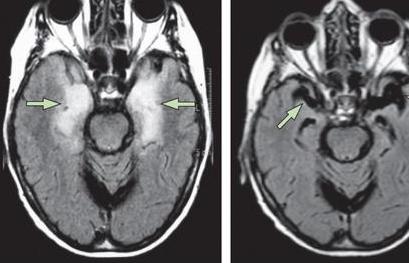

脑炎后遗症最好的康复医院 (脑炎后遗症比较厉害会永久瘫痪吗)

脑炎后遗症的出现对于患者的影响是很大的,对于每位脑炎后遗症患者来说,及时的接受正规专业的治疗是很关键的,也是很重要的,目前,治疗脑炎后遗症的方法是很多的,常见的方法包括免疫疗法、推拿疗法、对症治疗以及抗病毒治疗,这几种治疗方法的效果都是很不错的,下面我们就来进行一下详细的介绍,希望可以帮到大家。